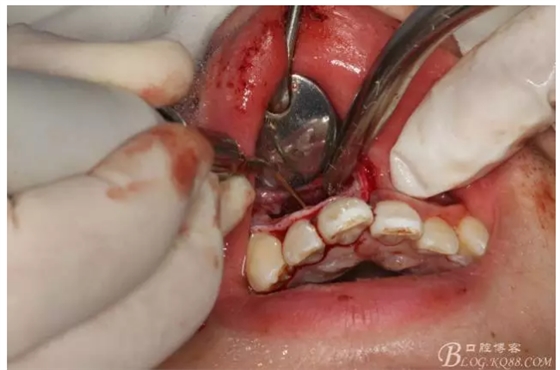

圖2.根管治療術(shù)后直接局部 麻醉下切開(kāi)、翻瓣,發(fā)現(xiàn)12唇側(cè)骨壁有綠豆大小骨缺損